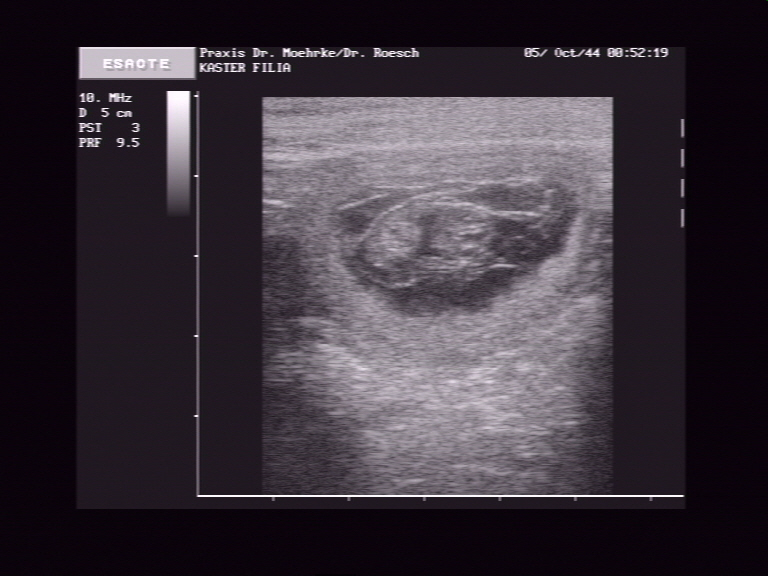

Ultraschall!

Heute sind wir zu Dr. Mörke nach Dortmund zum Ultraschall gefahren. Es war ein voller Erfolg. Wir haben viele Fruchtblasen mit herzaktiven Föten gesehen. Ganz toll! Über die gesehene Anzahl schweige ich mich erstmal aus :-)!

Es ist schon ein kleines Bäuchlein zu sehen bzw. zu fühlen!